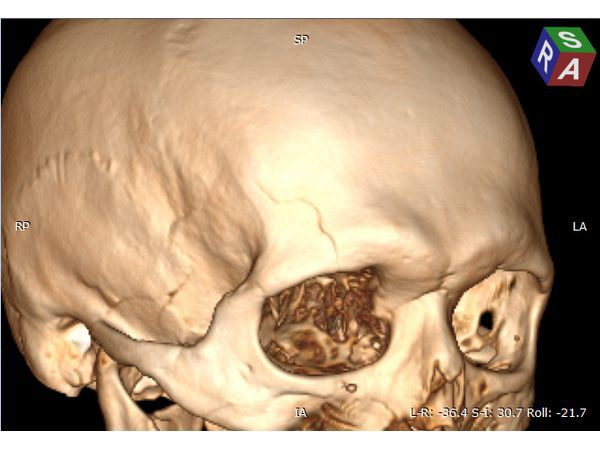

Техническая сложность заключалась в широких лобных пазухах пациента, т. к. фрезевое отверстие весьма желательно было наложить, не вскрывая лобную пазуху, но в то же время непосредственно в проекции внутримозговой гематомы. Для этого выполнена предоперационная разметка проекции внутримозговой гематомы на свод черепа.

Предоперационная 3D-разметка позволила рассчитать доступ — непосредственно в проекции внутримозговой гематомы, но без вскрытия лобной пазухи.